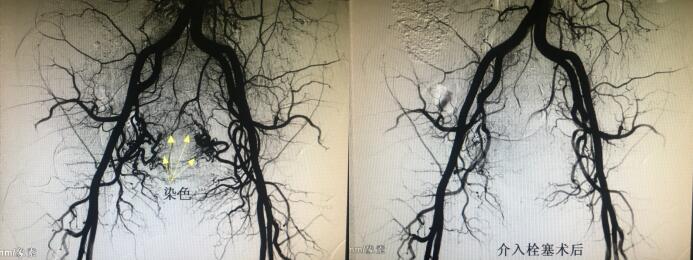

经人介绍来到乐鱼在线登录入口介入科,经李建国主任术前评估,患者无介入手术禁忌症,于4月16日早9点行介入手术。术中采用右肱动脉穿刺、超选择双侧子宫动脉造影栓塞术,手术顺利历时约40分钟,成功保全了子宫。术后患者步入病房,避免了因卧床制动而形成下肢深静脉血栓的风险...